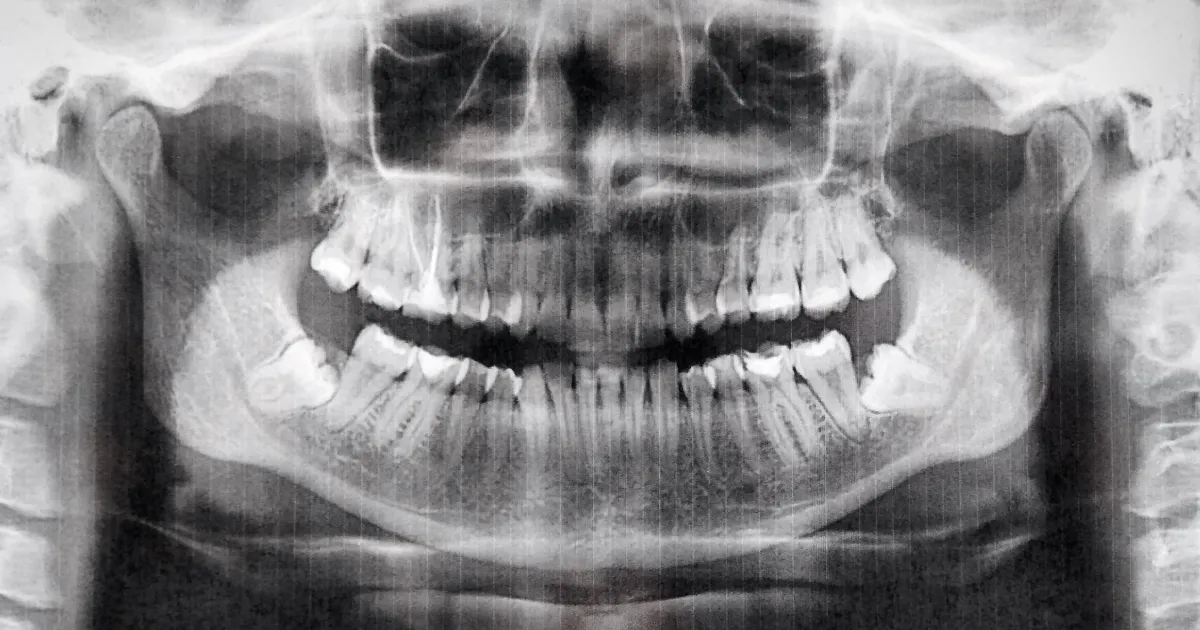

歯科ハミール高田88では、CT撮影や最新の3Dスキャナー「iTero」を導入しており、抜歯前の詳細な診断を行います。

これにより、歯の位置や形状、周囲の骨構造を正確に把握し、リスクを最小限に抑えた安全で確実な治療が可能です。

CTによる立体画像解析により、神経や血管の位置も明確にし、難易度の高い親知らずの抜歯にも対応しています。

この先端技術により、術後の合併症リスクも大幅に低減できます。